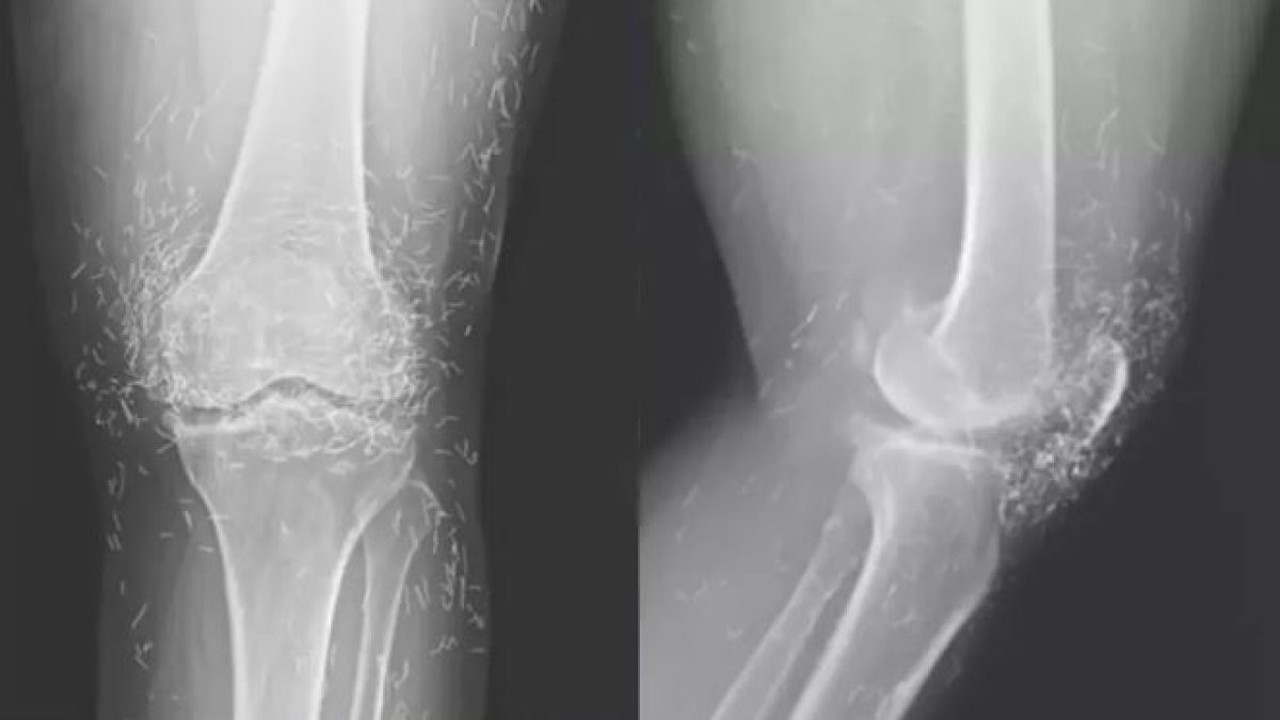

Görüntülerde ayrıca kemiklerde kalınlaşma, sertleşme ve mahmuz benzeri çıkıntılar belirlendi. Altın ipliklerin sebebinin ise alternatif bir tedavi olduğu anlaşıldı.

Hastanedeki tetkikler, röntgendeki altın ipliklerin kadının düzenli olarak yaptırdığı altın iplik akupunkturu seanslarında kasıtlı olarak bırakıldığını ortaya koydu. Bu yöntemde, steril kısa altın iplikler dokuya yerleştirilerek sürekli uyarım sağlanması hedefleniyor.

Ayrıca bu iplikler, görüntüleme teknikleri üzerinde olumsuz etkiler yaratabiliyor. Röntgen yorumlarını zorlaştırmasının yanı sıra, manyetik rezonans (MR) görüntülemelerinde ipliklerin hareket ederek damarlara zarar verme riski taşıdığı ifade edildi.

Doktorlar, bu tür geleneksel tedavilere başvuran hastalarda altın ipliklerin varlığının mutlaka dikkate alınması gerektiğini vurguluyor. Neyse ki iplikler röntgende kolayca görülüyor ve konumları takip edilebiliyor.